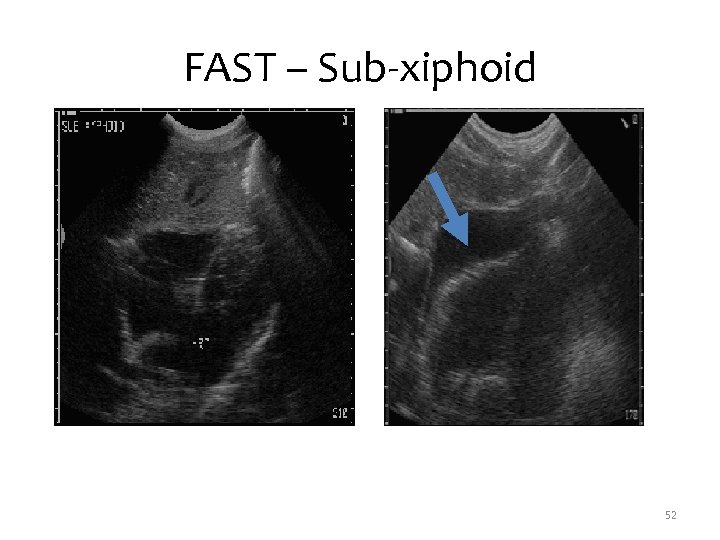

FAST – Sub-xiphoid • Evaluate for pericardial fluid • View through liver – Transhepatic or Parasternal • Searches for fluid between heart and pericardium 51

FAST – Sub-xiphoid 52